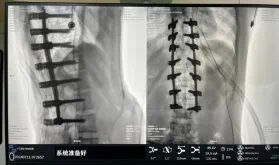

据悉脊柱侧弯手术治疗后可以坚持躯干平衡,,,,,改善外观并避免畸形进一步生长。。。。。唬唬唬唬唬患者的生涯质量获得提高,,,,,进而镌汰脊柱太过畸形可能带来的疾病的爆发率,,,,,外观上的起劲转变往往也能带来患者心理与精神的起劲转变。。。。。临床上会综合思量患者的年岁、侧弯水平、希望趋势、骨质条件、相近节段情形、手术节段等因素,,,,,合理接纳个性化的手术方法举行治疗。。。。。然而,,,,,由于脊柱神经血管密布,,,,,手术操作相对重大,,,,,手术难度高、危害大,,,,,古板脊柱侧弯的手术方法往往有较高的神经或脊髓损伤危害。。。。。故此次科室决议开展机械人辅助导航下脊柱侧弯矫形、植骨融合内牢靠手术。。。。。术前,,,,,医生团队在机械人多维度图像融合智能手术妄想功效的辅助下,,,,,预先妄想了理想的置钉路径。。。。。术中,,,,,天玑骨科手术机械人准确遵照术前妄想,,,,,凭证配准效果,,,,,实时定位并准确执行置钉操作,,,,,所有导针均用电钻置入,,,,,一次性乐成,,,,,协助医生顺遂完成手术。。。。。最终,,,,,在麻醉科、手术室亲近配合下,,,,,历时3小时乐成完成侧弯矫形术,,,,,出血量仅500ml。。。。。术后,,,,,患者恢复优异,,,,,巨细便及下肢神经运动感受正常。。。。。

图为置钉后